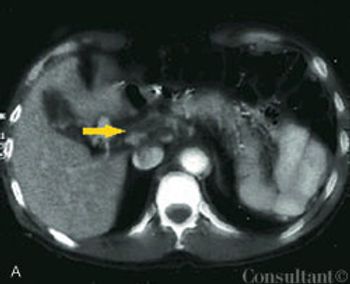

A 41-year-old man complained of upper abdominal pain and malaise of several months duration. He had emigrated to the United States from Korea 5 years earlier.